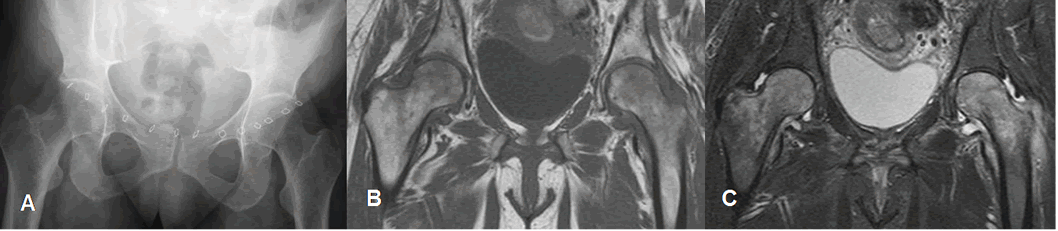

Fig 88 A. Osteoporosis transitoria.

A: Rx AP. Paciente postcesárea, con dolor en ambas caderas. Se aprecia moderada osteopenia, en las cabezas femorales.

B: RM coronal en T1 y C: RM coronal en STIR. Edema en ambas cabezas femorales, con moderado derrame asociado.